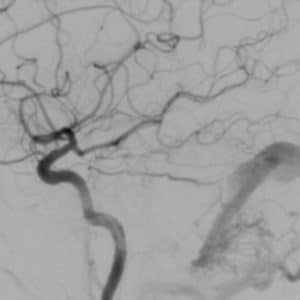

Brain Dural Arteriovenous Fistula